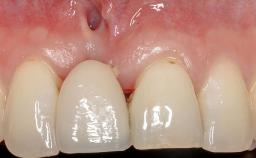

Paolo Casentini demonstrates that peri-implantitis can be successfully treated even at an advanced stage. He discusses a case in which the existing implants and prostheses were both retained while regenerating the defect and creating a band of keratinized tissue. A 69-year-old female patient was referred by her general dentist for evaluation of a recurrent infection at previously placed and restored implants in the posterior left mandible. The patient’s chief complaint was recurrent swelling and pain in the molar region of the left posterior mandible with discomfort during brushing in the same area. The patient reported receiving two implants (36 and 37) nine years earlier.